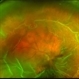

- retinal detachment, retinal holes

- Fundus photograph of a 40 year old male with a total retinal detachment with macula off with a HST at 1 o clock and a break at mid periphery at 8 o clock.